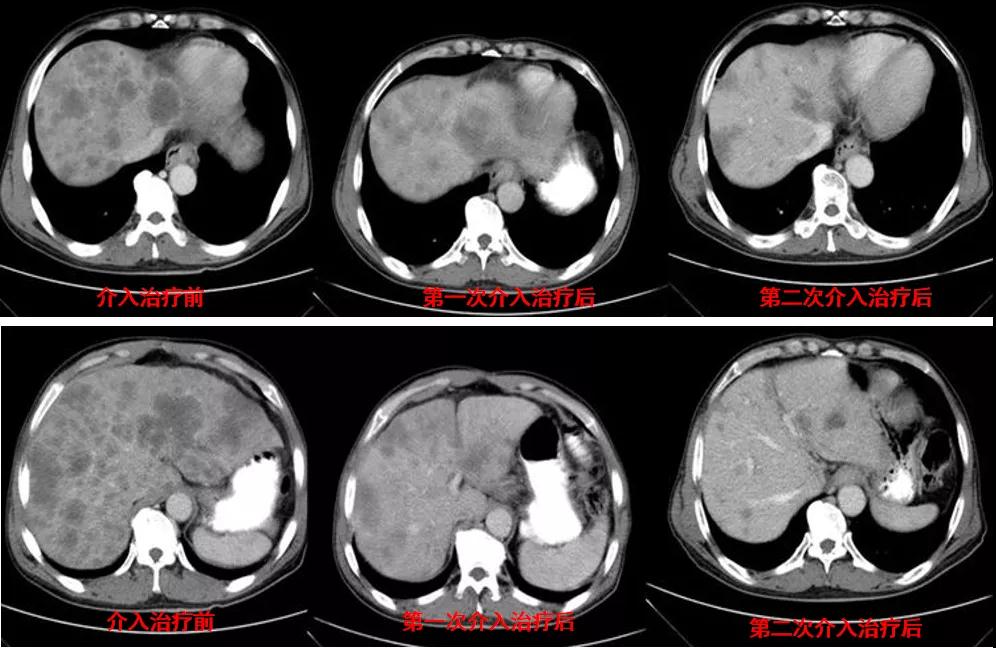

诊治经过:2020年11月25日患者行经皮动脉化疗灌注栓塞术(铂类+氟尿嘧啶);2020年11月30日免疫组化及基因检测结果为:ERBB-2扩增(9倍),VEGFR未突变,MSI微卫星低度不稳定,错配修复蛋白部分缺失(dMMR),MSH2(+弱),MLH1(-),MSH6(+),PMS2(-),CDX2(-),Villin(+),CK8/18(+),Ki67(5%+),CD56(-),Syn(-),CgA(-);患者为HER2阳性,患者肝脏病灶很多,残余正常肝脏体积小,需要寻找对肝功能影响小且抗瘤效果明显的治疗,因此联合吡咯替尼进行系统治疗。2020年12月14日复查结果提示肝脏病灶明显缩小(PR)。结果见图2。

图2

讨论:2020年12月14日患者复查示原发灶稳定,肝转移灶明显缩小,达到PR。患者一般状况好(ECOG:0分),治疗疗效显著,转移病灶多发且MSI微卫星不稳定为低度不稳定,因此不建议行外科手术及免疫治疗,继续行当前介入联合靶向治疗。